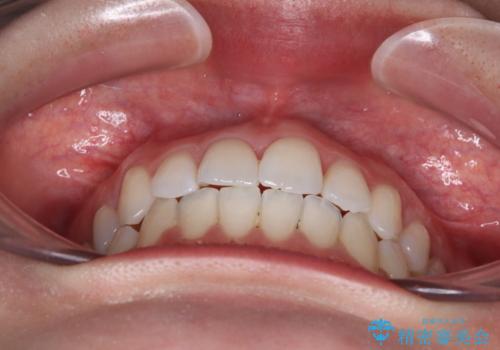

急速拡大装置により骨格はある程度改善されましたが、奥歯の咬み合わせ改善に非常に時間がかかってしまいました。

デコボコを改善させるだけでなく、しっかりとした咬合状態を獲得することができ、患者様には大変満足していただけました。